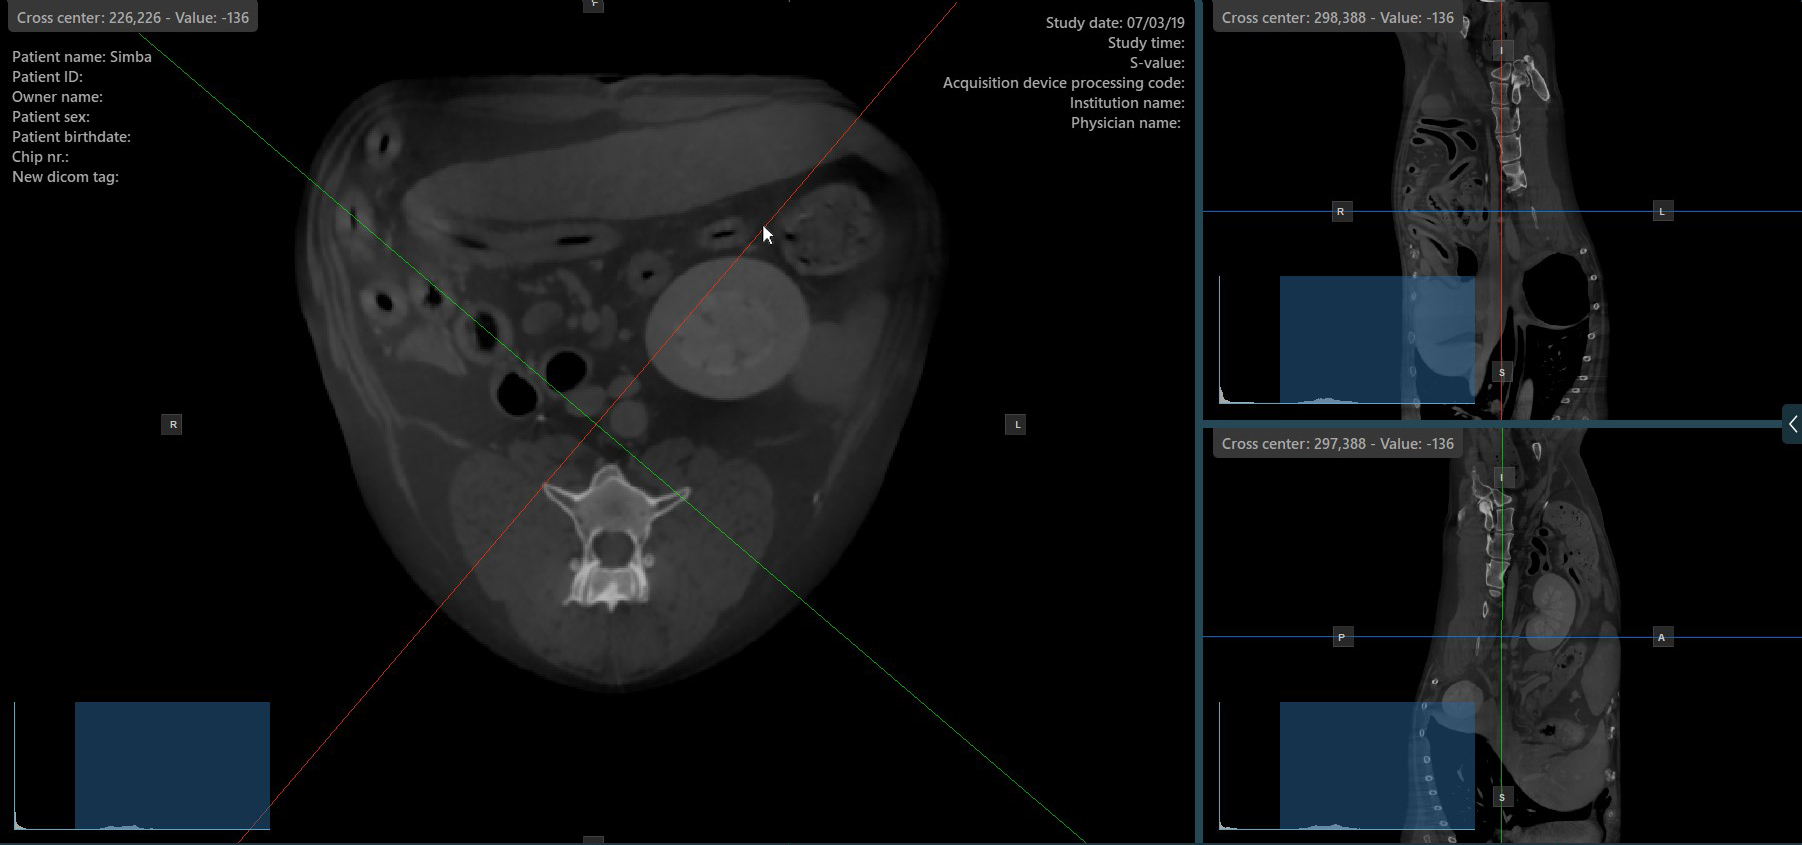

Altering the rotation of a slicer will change the orientation of the corresponding image planes. Individual slicers can be selected by using the Select Item (Default) tool, assigned to the right mouse button by default.

Once the specific slicer is selected, drag the slicer in the desired direction to rotate it. The corresponding image plane’s orientation changes accordingly.

By default, each slicer can be rotated separately. The corresponding icon in the left toolbar of the CT Viewer will be deselected when the slicers are rotated individually.

Press the Perpendicular Slicers icon in the left toolbar to activate simultaneous rotation of the slicers. Regardless of their previous orientation, the slicers are repositioned to be perpendicular to each other.

Toggle the Perpendicular Slicers option to switch the active mode of the slicers at any time, or choose one of the Tools -> Perpendicular Slicers or Tools -> Separate Slicers options from the CT Viewer menu.